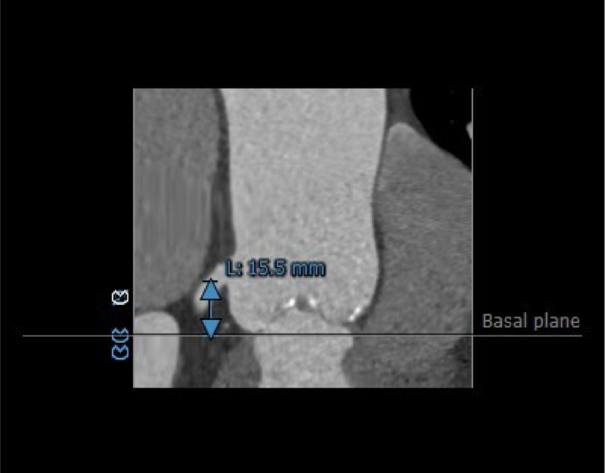

主动脉瓣瓣环周长77.4mm,平均周长径24.6mm。CT数据显示该患者为Type1型二叶式主动脉瓣,瓣叶轻度增厚,中度钙化,钙化分布散在分布于瓣叶边缘,左右瓣叶交界区钙化分布较重,左右瓣叶融合并形成坚强钙化嵴,左右冠开口高度可,未见冗长瓣叶,冠状动脉散在钙化。

主动脉根部评估

左右冠脉高度